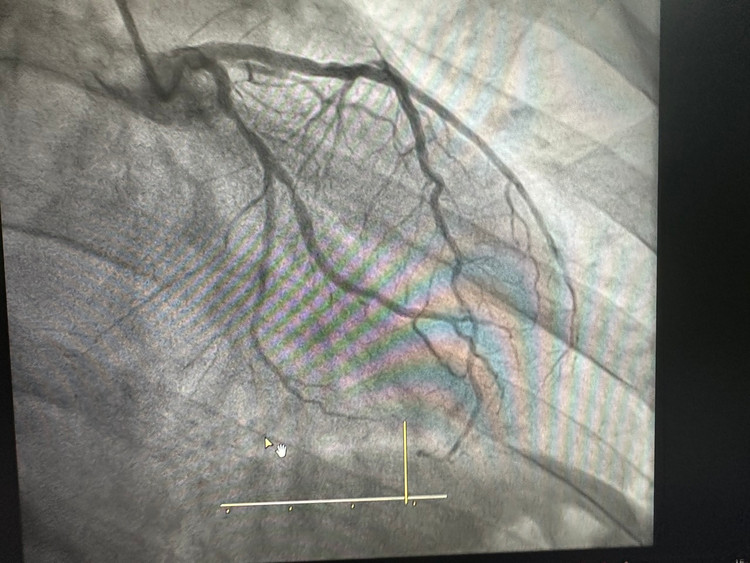

Chụp động mạch vành qua da cho hình ảnh hẹp 95%RCA(p),70%LCX(p),80%OM(p). Bệnh nhân được tiến hành đặt máy tạo nhịp tạm thời chủ động kết hợp can thiệp động mạch vành.

Bác sĩ Piter cùng cộng sự khoa Tim mạch đã thành công đặt 01 stent vị trí RCA(p), sau can thiệp chụp kiểm tra dòng chảy tái thông tốt, BN không còn đau ngực, huyết động ổn định, đã được chuyển về khoa Tim Mạch theo dõi và điều trị.

| Hình ảnh trước và sau đặt stent |